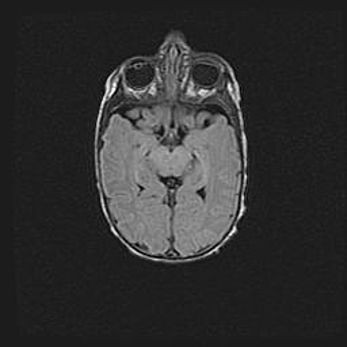

Множественные мелкие кисты перивентрикулярной области.

Киста прозрачной перегородки.

Возраст: 28 дней

Вес: 2400 г

Пол: женский

Окружность головы: 33 см

Срок гестации: 34 недели

Перивентрикулярная киста – это полостное образование в околожелудочковых областях белового вещества головного мозга. С морфологической точки зрения – это мелкоочаговая зона коагуляционного некроза, возникшая после инфаркта белого вещества. Наиболее часто поражаются начальные отделы задних рогов боковых желудочков. Обычно образования заполнены жидкостным содержимым.

Киста прозрачной перегородки может располагаться в переднем отделе межжелудочковой перегородки, в области мозолистого тела и мозжечка.